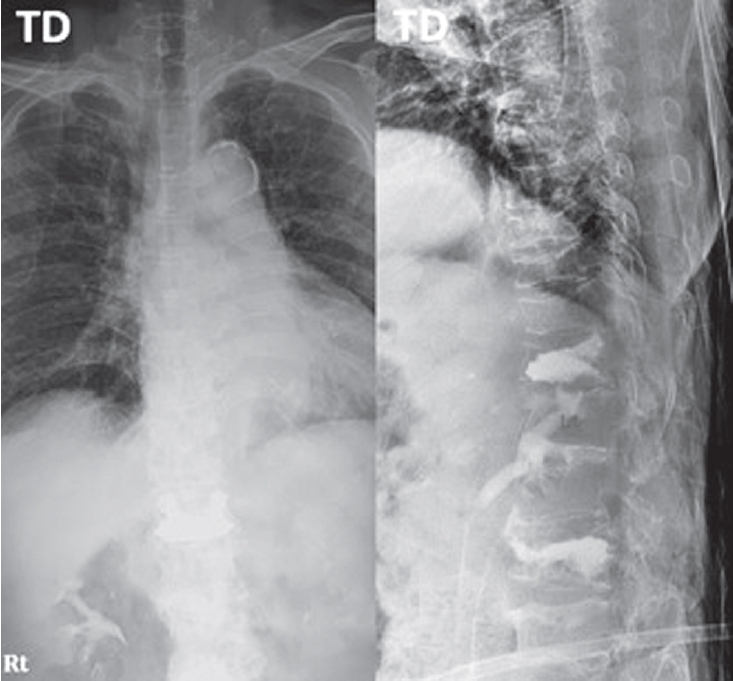

Spine-Shortening Osteotomy for Recurrent Adult Tethered Cord Syndrome Exacerbated by Traumatic Kyphosis: A Case Report

Tethered cord syndrome (TCS) is a condition in which the spinal cord becomes pathologically stretched due to various congenital or acquired etiologies, leading to progressive neurological symptoms. While surgical detethering is the gold standard for pediatric patients, adult-onset recurrent TCS presents a significant surgical challenge. Reoperation carries substantial risks—including spinal cord injury, cerebrospinal fluid leakage, and a high rate of retethering—often resulting in suboptimal long-term outcomes. Recently, spine-shortening osteotomy (SSO) has emerged as an alternative technique to reduce spinal cord tension without direct manipulation of the neural elements. Here, we report a case of recurrent adult TCS associated with a lipomyelomeningocele, which was exacerbated by post-traumatic kyphosis from an L1 compression fracture. The patient was successfully treated with SSO at the L1 level. This case highlights the utility of SSO as a safe and effective alternative to conventional revision detethering, particularly in complex cases involving spinal deformity.